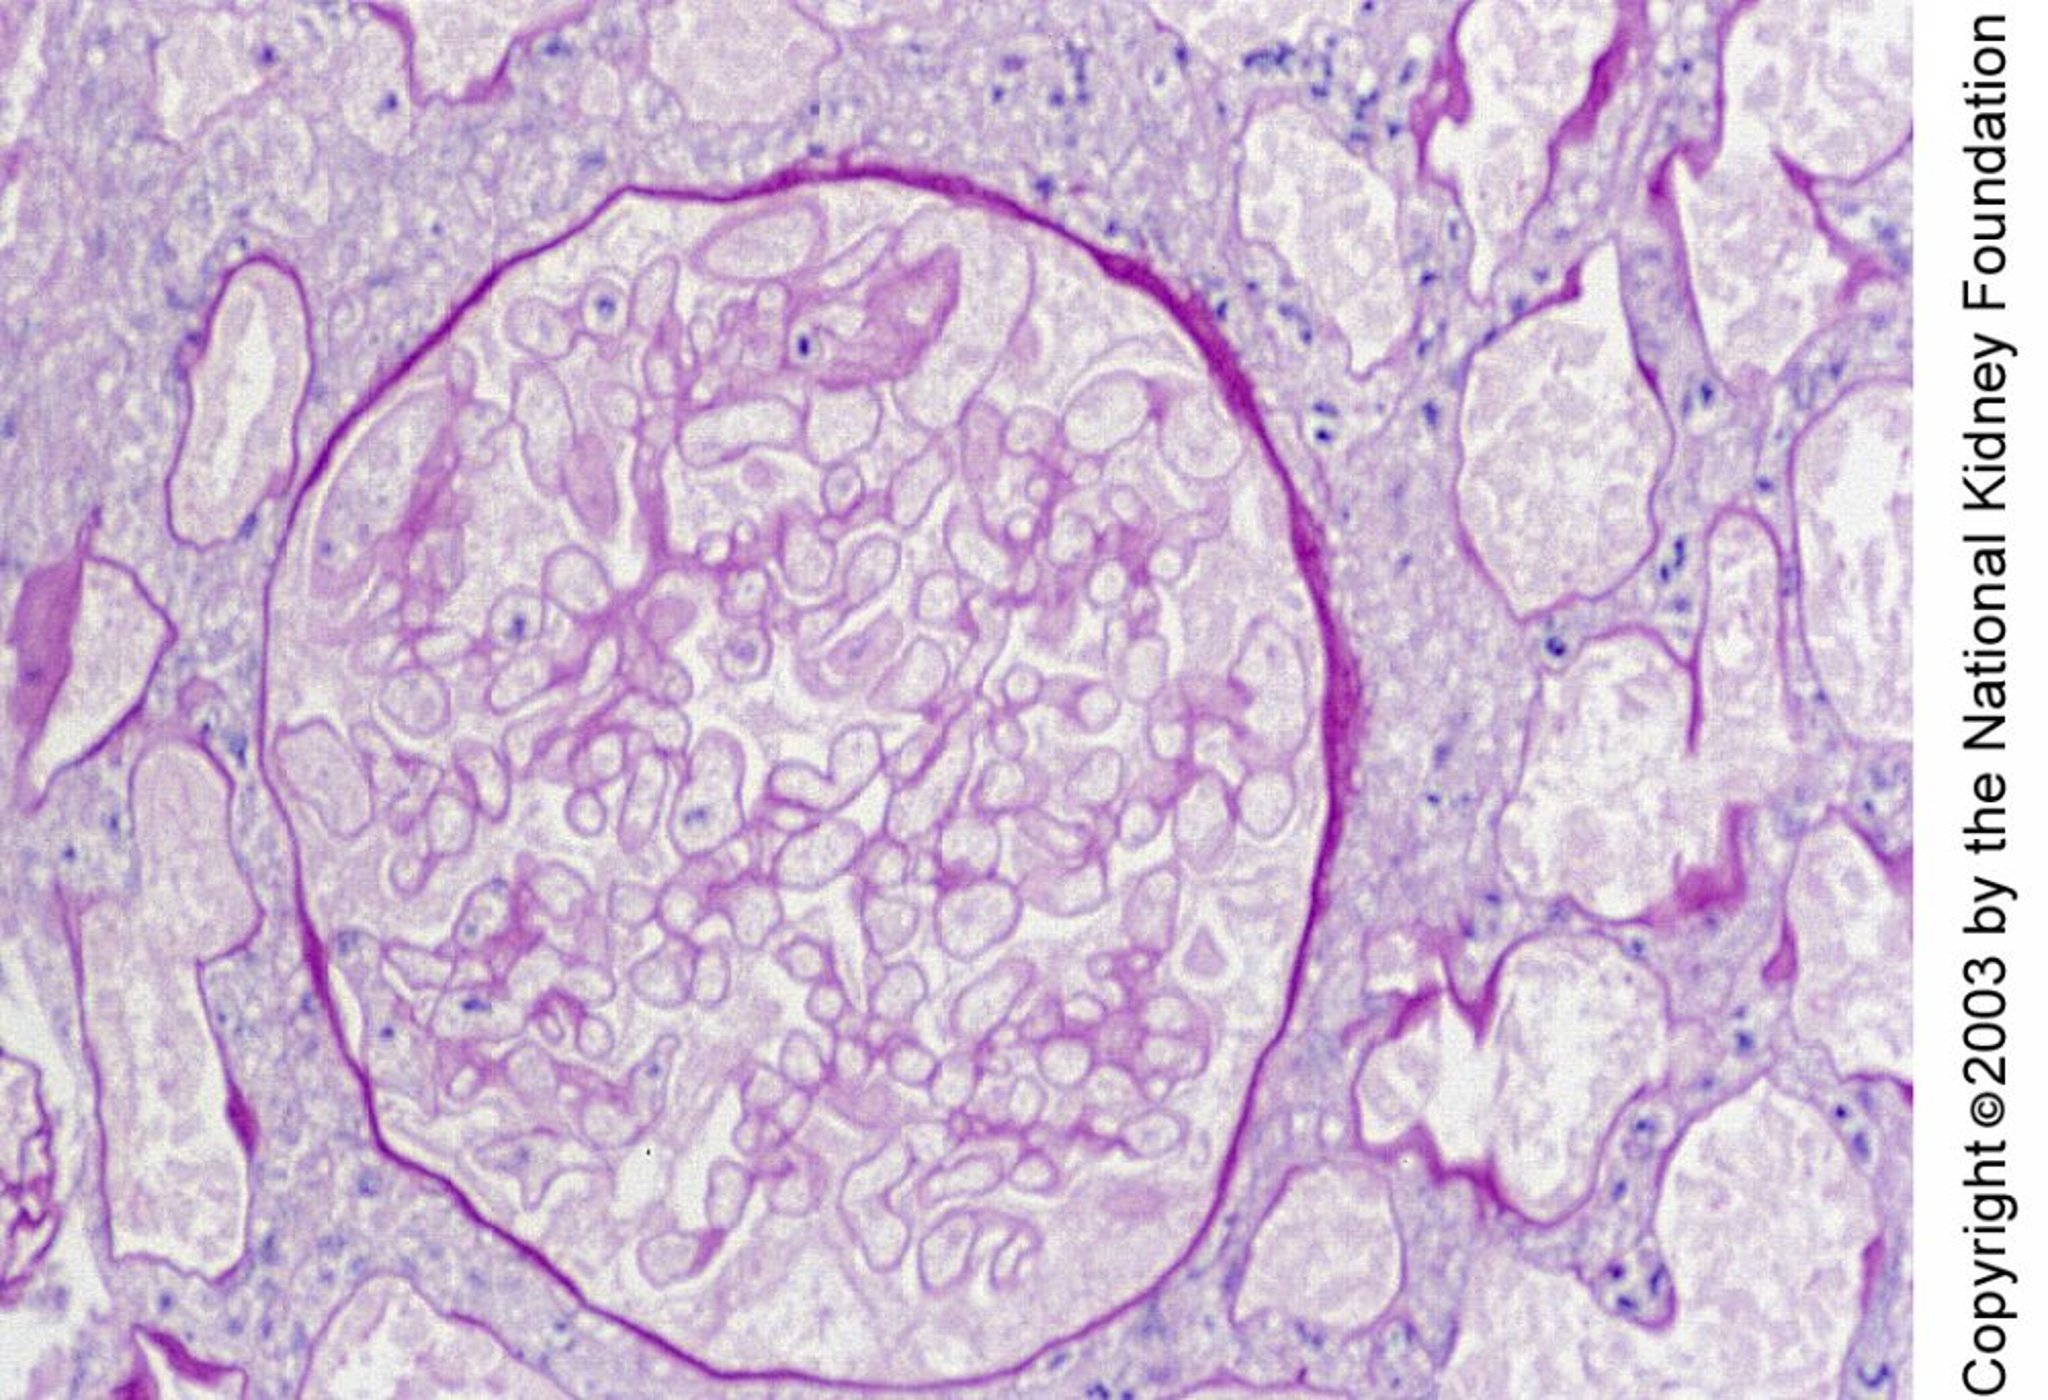

Necrosis cortical renal

La necrosis cortical renal se caracteriza histológicamente por necrosis de los glomérulos y los túbulos. En esta pieza de biopsia la necrosis se manifiesta por núcleos pequeños y contornos de células fantasma (tinción de ácido peryódico de Schiff, × 400).

Image provided by Agnes Fogo, MD, and the American Journal of Kidney Diseases' Atlas of Renal Pathology (véase www.ajkd.org).